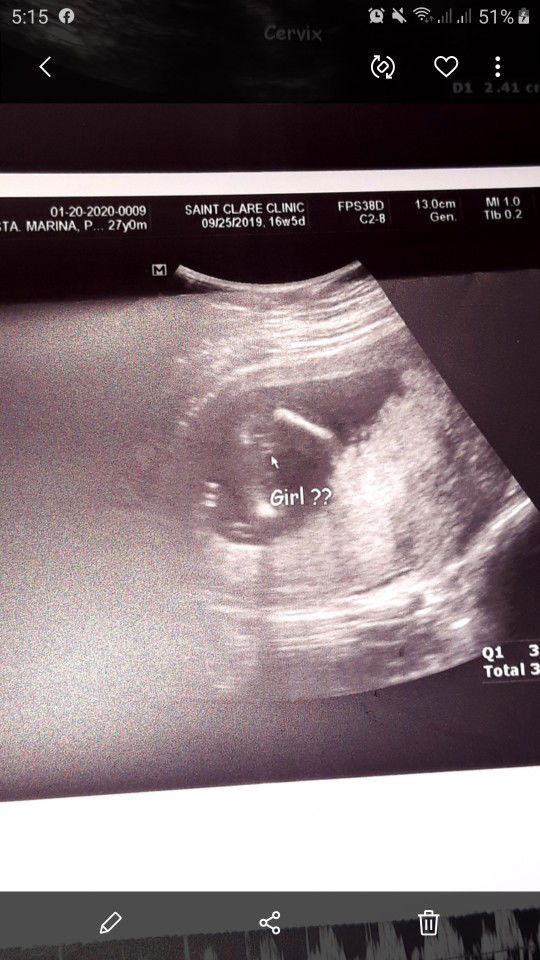

16weeks 4days Pelvic Ultrasound(BabyGirl??)

Sa 16weeks po ba or 4months.. possible ba makita na ang sure Gender ni Baby.. Sabi ni OB me hiwa daw,most likely babae daw dalawa beses nya sinipat. Pero masyado padaw maaga. Excited kasi po ako sa Baby Girl at Boy kasi ang panganay ko tapus 9years old na kasi.?

16weeks 4days Pelvic Ultrasound

Baka po me marunong bumasa ng Ultrasound ko. Sa Friday pa po kasi ako babalik sa OB ko. Medyu kinabahan ako sa Previa. Kahit sabi ng Doc.nagultrasound na iikot pa nmn ang bata. Need Advice po..

placenta previa po grade 1 ibig sabihin yng placenta ni baby mababa and covers the cervix partially.. maaga pa nmn po, kadalasan na reresolve dn mga ganito pro double ingat lng